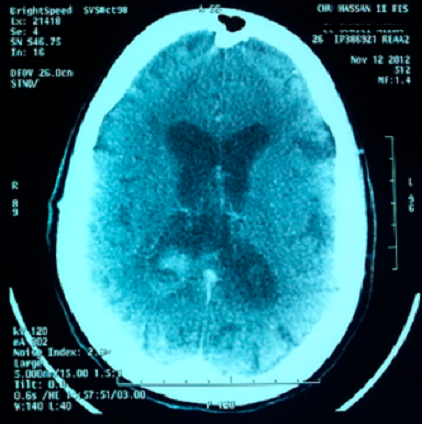

Vascularite cérébrale est souvent difficile à diagnostiquer et peut nécessiter une batterie de tests Les médecins peuvent utiliser une tomodensitométrie (TDM) et l’imagerie par résonance magnétique (IRM) Une ponction lombaire ou l’analyse du liquide céphalorachidien, peut aussi indiquer une éventuelle maladie neurologique. Accident vasculaire cérébral ischémique – L’étiologie, la physiopathologie, les symptômes, les signes, les diagnostics et les pronostics à partir des Manuels Merck, version pour professionnels de la santé. Les vascularites sont des maladies rares autoimmunes Le "ite" veut dire inflammation, on est donc en présence d'une inflammation vasculaire, ou, pour être plus précis, d'une inflammation de la paroi des vaisseaux sanguins.

Vascularite cérébrale est souvent difficile à diagnostiquer et peut nécessiter une batterie de tests Les médecins peuvent utiliser une tomodensitométrie (TDM) et l’imagerie par résonance magnétique (IRM) Une ponction lombaire ou l’analyse du liquide céphalorachidien, peut aussi indiquer une éventuelle maladie neurologique. Pour toutes questions sur le GFEV, les vascularites ou les protocoles en cours GFEV Groupe Français d'Etude des Vascularites Service de Médecine Interne Hôpital Cochin Bâtiment Saint Jacques 27, rue du faubourg Saint Jacques Paris cedex 14 Tél 33 1 58 41 29 71 Fax 33 1 58 41 29 68 groupevascularite@cchaphpfr. Vascularite cérébrale est souvent difficile à diagnostiquer et peut nécessiter une batterie de tests Les médecins peuvent utiliser une tomodensitométrie (TDM) et l’imagerie par résonance magnétique (IRM) Une ponction lombaire ou l’analyse du liquide céphalorachidien, peut aussi indiquer une éventuelle maladie neurologique.

Une angiographie cérébrale peut être effectuée avant l’ablation chirurgicale d’athéromes ou en cas de suspicion de vascularite Comme l’angiographie par TDM est moins invasive, elle a largement remplacé l’angiographie cérébrale réalisée avec un cathéter. 3 Hémorragie cérébrale ou intracérébrale Parmi les maladies vasculaires cérébrales, on retrouve l’hémorragie cérébrale Nous avons parlé des deux maladies cérébrales d’origine ischémique les plus communes Nous nous arrêtons désormais sur ces problèmes dont les éléments déclencheurs sont dus à une hémorragie. Près de 80% des patients atteints de vascularite ont des changements EEG diffus, mais cette méthode avec vascularite cérébrale n'est ni spécifique ni sensible et ne fournit pas de précision diagnostique( Joseph FG Scolding NJ vasculite cérébrale une approche pratique // Pract Neurol 02 Vol2 P8093 ).